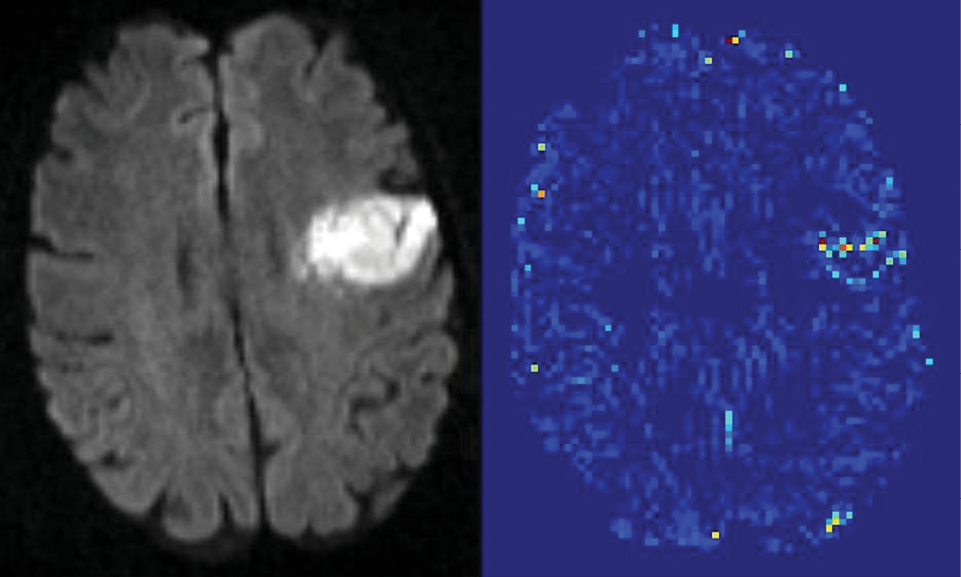

A new MR imaging technique that quantifies blood-brain barrier (BBB) damage may expand treatment for acute ischemic stroke (AIS) patients by more precisely determining risk factors associated with a common blood-clot busting drug treatment, new research shows.

Researchers at Johns Hopkins University School of Medicine used the novel MR imaging technique to determine with 95 percent statistical certainty a leakage amount associated with the side effects of tissue plasminogen activator (tPA) treatment, which breaks down blood clots. Currently, tPA is the only FDA-approved treatment for ischemic stroke.

Researchers analyzed the data of acute ischemic stroke patients provided by the Stroke Imaging Repository and Virtual International Stroke Trials Archive. The images were then divided into three groups according to ECASS criteria: no hemorrhage, hemorrhagic infarction and parenchymal hematoma. Next, researchers developed an algorithm that uses an arrival time correction quantitatively to remove the effects of blood flow and dispersion from the recorded signal, allowing an index related to BBB permeability to be estimated.

The analysis quantified a threshold of BBB damage after which tPA treatment harms a patient. “When a mean permeability was elevated to 20 percent, then that was associated with the larger hemorrhages,” Dr. Leigh said.

Another key finding: the study quantified that not all BBB damage is the same, Dr. Leigh said. The detail provided by MR imaging scans enabled researchers to classify the severity of BBB damage. “Mild blood-brain-barrier damage was not necessarily a bad thing according to our analysis, which is a little counterintuitive because it is currently thought of as all bad,” Dr. Leigh said. The idea of “mild blood-brain barrier damage” points to the need for further study, he said.